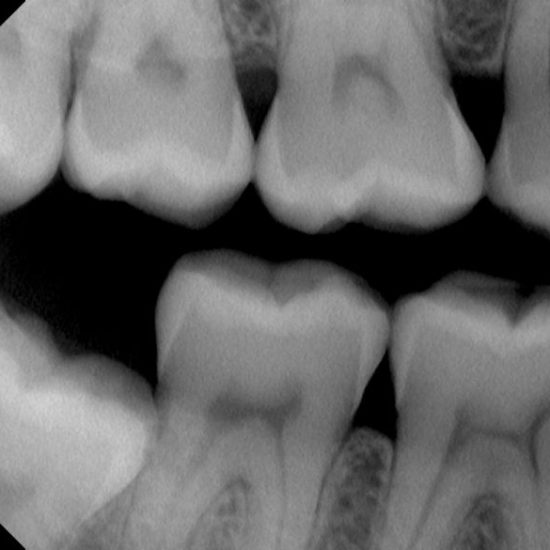

BITEWING ali TEHNIKA ZAGRIZA

Tehnika s katero analiziramo več zobnih kron sosednjih zob in zob v nasprotni čeljusti. Ker je vpadni kot rentgenskih žarkov pravokoten na zobne krone zelo natančno pove ali imamo karies v medzobnih ploskvah ali ne. Zobozdravnik se namreč pogosto težko odloči in želi ta posnetek, da ne bi zaradi napačne diagnoze saniral v zdrav zob.